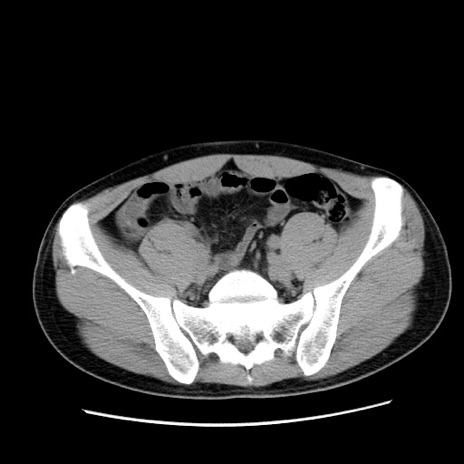

冠状断像

【症例】20歳代 男性

【主訴】心窩部痛

【現病歴】今朝より上腹部痛あり。一旦軽快していたが再度出現したため救急要請。昨日夕に白身の魚を含む刺身を食べた。

【身体所見】BP 136/89mmHg、HR 74/min、BT 37.0℃、腹部:膨満、軟、心窩部に圧痛あり。反跳痛なし、筋性防御なし、腸雑音やや亢進あり。

【データ】WBC 17700、CRP 0.48